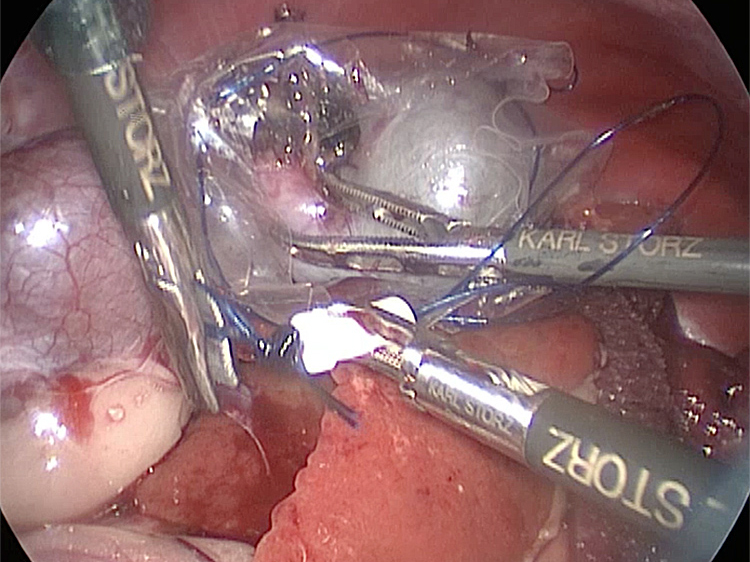

お腹にトロッカーを4本挿入し、そこから鉗子とカメラを入れて胆嚢を肝臓から剥がしていきます。 カメラで拡大しながら見ることができるので開腹手術よりも視野が確保できます。

手術の様子

胆嚢の頸部に糸を通し動脈を確保しています。